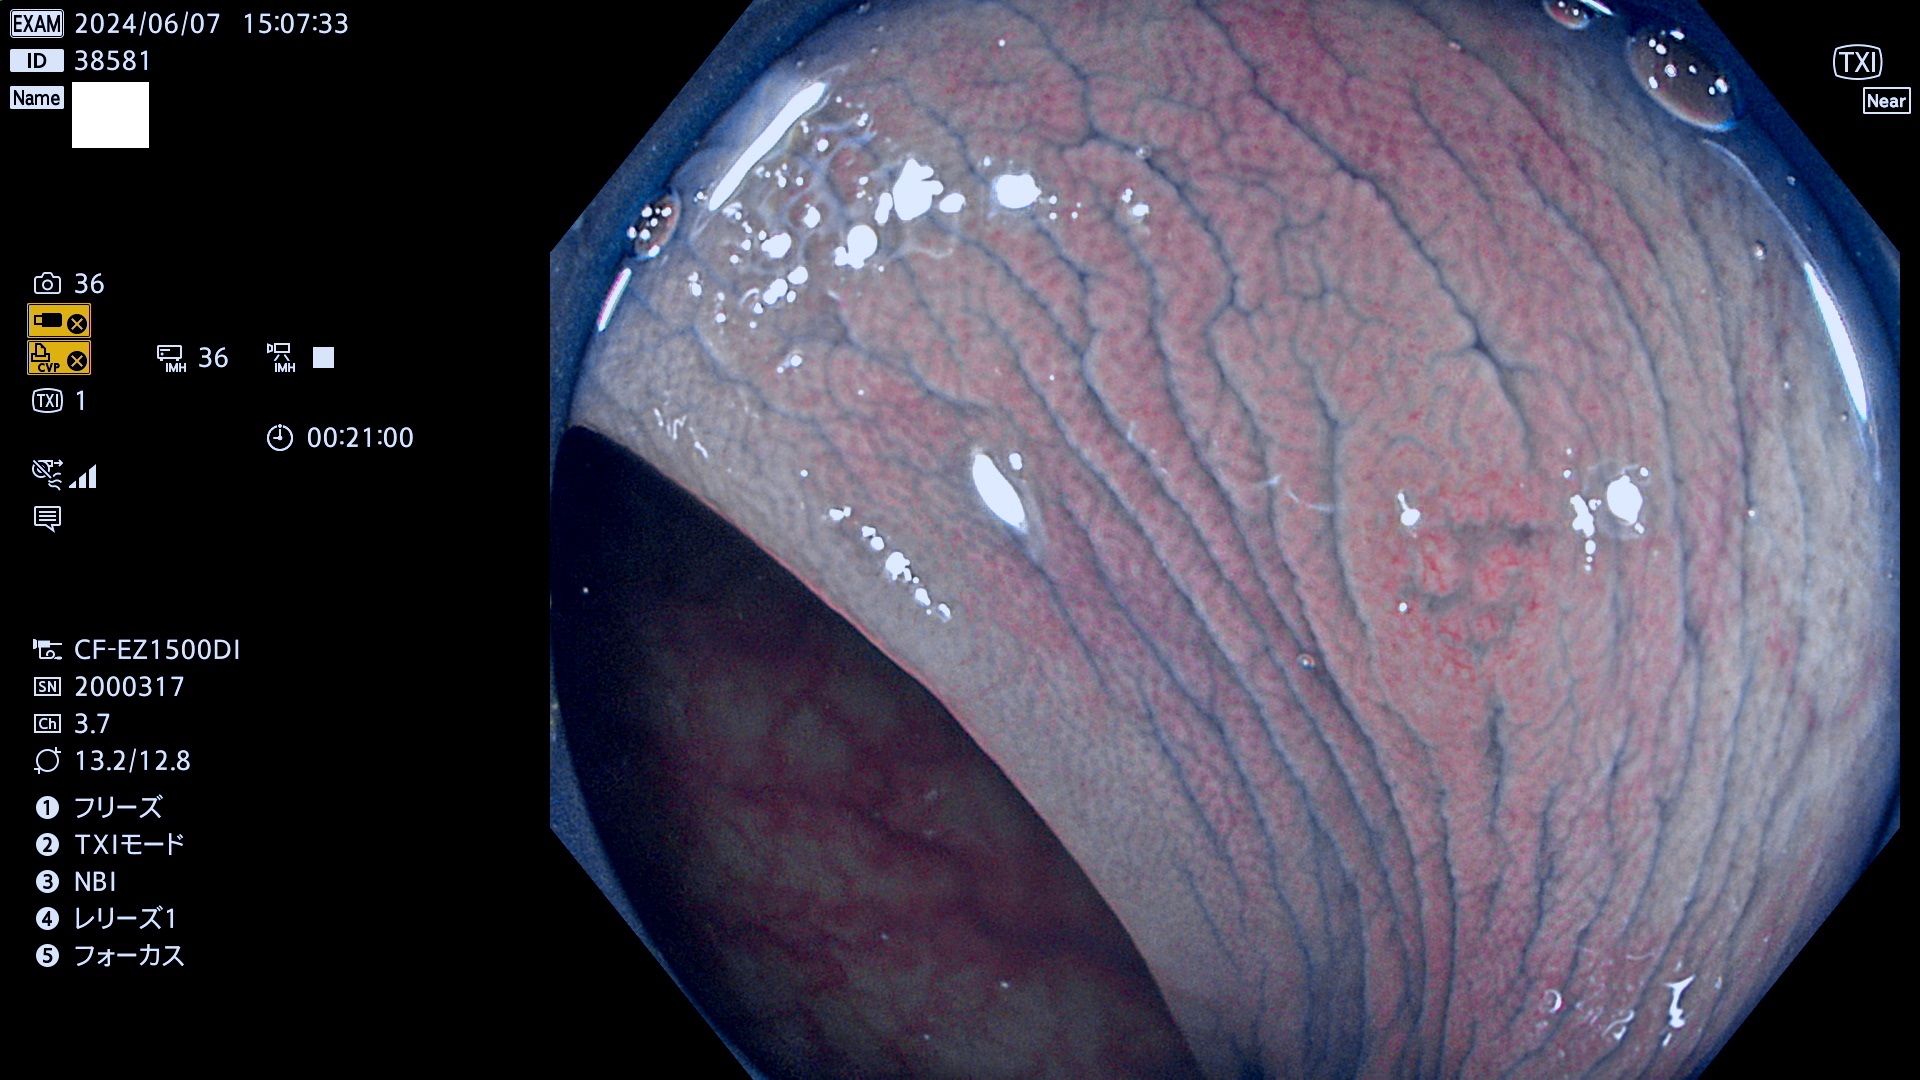

今週のUb、Uc型腺腫

表面型腺腫(Flat Adenoma)の中で、完全に平坦な物をUb、陥凹している物をUcと呼びます。平坦隆起型(Ua)よりも、発見が難しく危険な病変です。

毎週の検査(木・金・土・日)に発見されたUb、Uc型・腺腫を、その週の日曜の夜にUPし1週間、提示します。

抽出の対象期間 2024年6月6日〜6月10の5日間(50件の検査)7件 (7/50=14%)